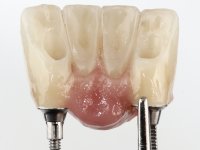

Faced with two possibilities, try to use the implant or remove it, I chose to remove it. Two reasons for this decision, first, the buccal bone loss was very extensive and second, the adjacent teeth had a poor prognosis in the medium term. In this sense, it was proposed to remove the implant, extract teeth 42 and 32, simultaneously place 2 implants in their place and immediately rehabilitate the area with a 4-piece screw-retained temporary bridge. After osseointegration, a 4-element screw-retained bridge would be made with ceramic in a coronal and gingival shade.

After an imaging study, the placement of two implants of 3.3 mm in diameter and 10 mm in length was planned. On the day of surgery, teeth 42 and 32 were extracted and the implant was removed. The implants were placed in the area of the alveoli, taking care to slightly lingualize their positioning. An impression was made using the open tray technique with the flap open for the fabrication of the immediate provisional bridge. While the impression was taken to the laboratory, tall healing screws were placed and the surgical wound was sutured. The patient waited 2 hours in the waiting room while the temporary bridge was made in the laboratory. An immediate screw-retained provisional bridge was placed and its seating was controlled by imaging. After 3 months, the final impression was made using an open tray technique. In this consultation, we took the opportunity to polish the temporary bridge with rubber cups so that the soft tissues could mature in better conditions. Information was collected to better characterize the monolithic structure in Zr. Color guides were used for the coronal and gingival ceramics. In the laboratory, a bridge was made in Zr. bolt-on that has been carefully characterized. After approval by the patient, it was definitively placed in the mouth. Tightening was performed with a dynamic wrench with a torque of 35 N. The holes were covered with Teflon and filled with composite resin.